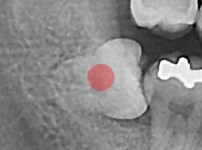

충치가 심한 사랑니

조회

876

작성일

25-12-03